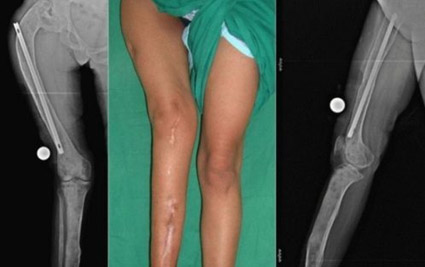

Врожденная дисплазия коленных суставов

Врожденные диспластические деформации коленных суставов составляют примерно 1,2% от всех врожденных заболеваний опорно-двигательной системы. Выделяют два основных типа деформации коленного сустава: вальгусный (Х-образный) и варусный (О-образный) (см. рисунок ниже).

Чаще всего дисплазия коленного сустава в раннем детстве протекает без явных симптомов. Однако с 2-3 лет, когда ребенок начинает активно передвигаться, проявления заболевания становятся более заметными. У детей наблюдается фронтальная деформация коленных суставов (одного или обоих), неуверенность при ходьбе, частые падения, легкая хромота и потеря равновесия при приседании.

При движении в колене могут слышаться характерные «пощелкивания». Со временем развивается сгибательная контрактура сустава, ограничивается ротация голени наружу и длина шага. По мере роста ребенка симптомы могут усиливаться, могут возникать боли в суставах, а также фиксироваться вывих надколенника, который смещается наружу и вверх.